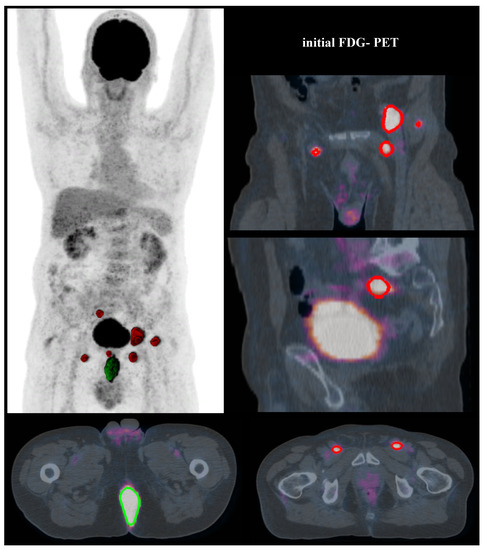

4.2. FDG-PET Acquisition

4.3. Interpretation of PET-CT Images and Segmentation Methods